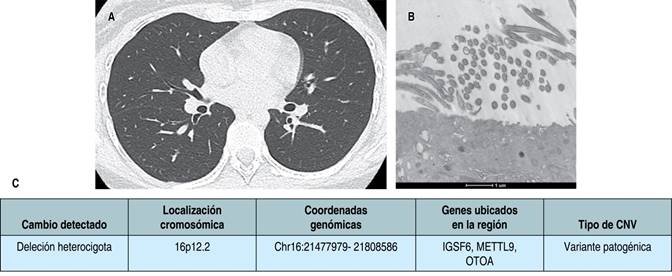

Caso 1: femenino de ocho años con antecedente de infecciones de vías respiratorias recurrentes desde el nacimiento, tres eventos de neumonía, dos de influenza y tres cuadros de otitis. Se realizó diagnóstico de asma por espirometría con obstrucción leve con respuesta positiva a broncodilatador, persistiendo con tos húmeda productiva a pesar de dosis altas de tratamiento de control de asma. De forma recurrente, presenta sibilancias y estertores gruesos. Se realizó abordaje con tomografía de tórax de alta resolución (TACAR) con presencia de bronquiectasias cilíndricas (Figura 1A), fueron descartadas patologías como fibrosis quística, inmunodeficiencias, reflujo gastroesofágico y aspergilosis broncopulmonar. Se realizó broncoscopia flexible para toma de biopsia de cilio (endobronquial), la cual se reportó con epitelio endobronquial con alteraciones ultraestructurales y de membrana compatible con discinesia ciliar (procesada por microscopia electrónica), con ausencia de brazos de dineína que corresponde a DCP tipo I según la clasificación de Barlocco y colaboradores8 (Figura 1B). Por parte del servicio de genética se realizó estudio molecular de panel de 538 genes por secuenciación de nueva generación para ciliopatías, el cual informó que la paciente es heterocigota compuesta para dos variantes en el gen DNAH5, la variante c.2578-2A>T está reportada previamente como patogénica; la variante c.1981C>A (p.Arg661Ser) está clasificada como de significado incierto (Figura 1C). Se establece diagnóstico de DCP y, con ello, la reducción de dosis de inhalador hasta el retiro; se inicia terapia de rehabilitación pulmonar y manejo de forma multidisciplinaria con los servicios de otorrinolaringología, audiología y cardiología pediátrica. Se descartó situs inversus.

Figura 1: A) Corte axial de tomografía computarizada pulmonar de alta resolución, en donde se observa bronquiectasia cilíndrica en hemitórax derecho; en la microscopia electrónica (B) se evidencia ausencia en los brazos de dineína. Discinesia ciliar primaria tipo I según la clasificación de las alteraciones ciliares modificada de Barlocco et al.8 El estudio genético (C) reportó dos variantes en el gen DNAH5, la variante c.2578-2A>T y la variante c.1981C>A (p.Arg661Ser).